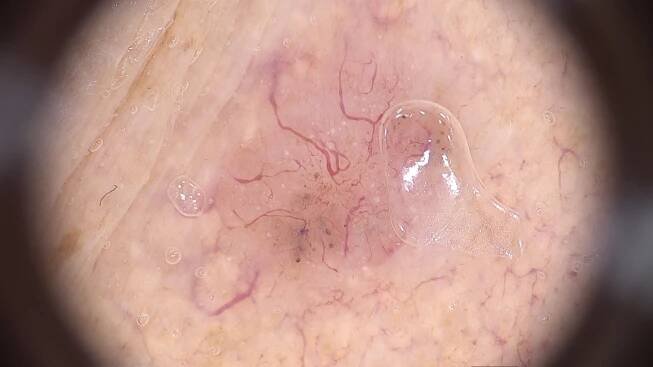

Co je hemangiom?Jako hemangiom se označuje nezhoubný mezenchymový nádor, který vzniká z krevních cév. Je obvykle plochý, mírně se vyklenuje nad povrch pokožky, může dosahovat velikosti několika centimetrů a mívá červenou, hnědočervenou nebo fialovou barvu. Z lékařského hlediska se jedná o vaskulární anomálii, která se obvykle tvoří na kůži nebo v podkoží (nejčastěji na hlavě a na krku), ale může vzniknout také na vnitřních orgánech, jako jsou játra, ledviny, mozek, hrtan či plíce.

Jak se liší kongenitální a infantilní hemangiom?Kongenitální hemangiom jsou lékaři obvykle schopní diagnostikovat již díky prenatálnímu ultrazvuku. Tyto léze totiž vznikají v průběhu nitroděložního vývoje a na pokožce dítěte jsou dobře patrné ihned po narození. Mívají okrouhlý či oválný tvar, přičemž barva se pohybuje od světle růžové až po temně fialovou. Infantilní hemangiom se na kůži často tvoří až během prvních týdnů nebo měsíců života novorozence. Roste velice rychle, poté se však jeho stav obvykle stabilizuje a začne se opět zmenšovat, což může trvat měsíce i roky.

Jak hemangiom poznáme?Hemangiom mívá červenou, červenohnědou či nafialovělou barvu. Velikost se obvykle pohybuje mezi několika milimetry až centimetry a při doteku dočasně zbledne.